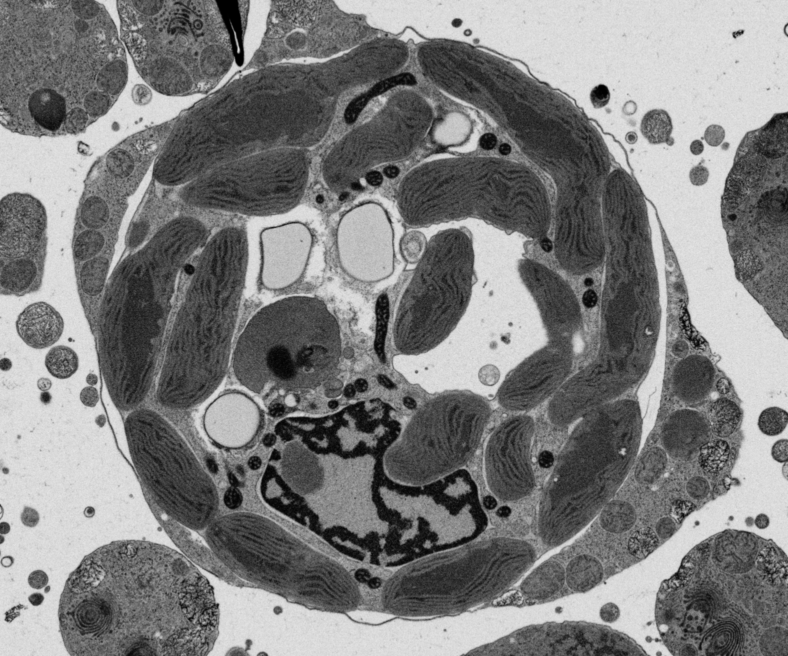

Actual z-index: 344Sampling: sampled from 682 source slicesScale: 20 x 20 x 20 nmContrast: source uint8. 8-bit source planes are written directly without intensity renormalization.Frame cache: warming 0/96Keyboard: ←/→ step, Home/End jump.